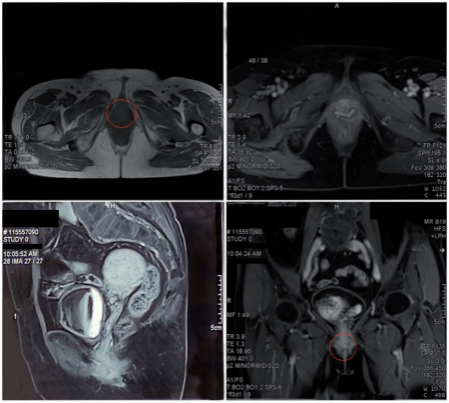

Figure 6. Gadolinium-enhanced magnetic resonance imaging 1 year after carbon ion radiotherapy showed that the lesion had completely disappeared.

During CIRT, dysuria and frequency (up to 9–10 times/day) occurred from the seventh fraction of treatment. These symptoms were considered to have been caused by radiation-induced urethral edema, and they were relieved by symptomatic treat ment. Skin and mucosal erythema in the irradiated field occurred 10 days after the start of CIRT, as did edema of the labia major and minor, the vaginal opening, and the urethral orifice around the lesion; these were assessed as grade 1 radiation dermatitis and mucositis. The skin and mucosal adverse effects were relieved 1 month after completion of CIRT, and the dermatitis, mucositis, dysuria, and frequency of urination were totally resolved 2 months after completion of CIRT (Figure 4). No other acute or chronic adverse effects of CIRT were observed. At the end of CIRT, the tumor treatment response was stable disease. Three months after completion of CIRT, the lesion was visually smaller than before, and MRI showed that the maximum tumor diameter was about 17mm with a 32% reduction (partial remission). The lesion completely disappeared 1 year after treatment (Table 1, Figure 5, and Figure 6). The patient declined other systemic treatment after CIRT for personal reasons. As of November 2021, 33 months after CIRT, the patient was alive and disease-free. She was satisfied with the outcome of CIRT. No severe reactions were observed.